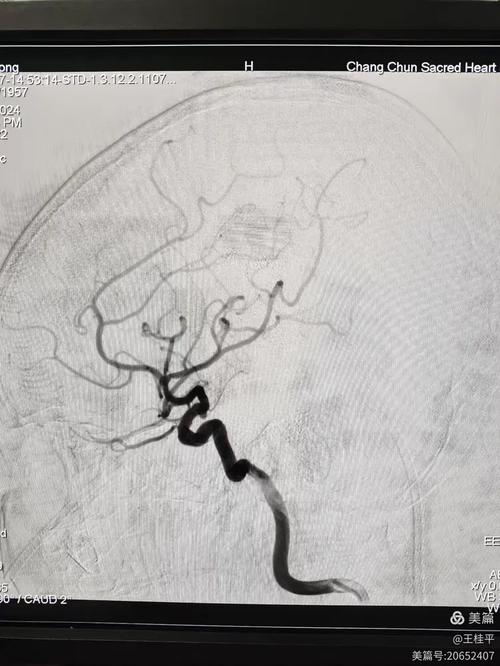

- 脑动脉血管瘤:它不是肿瘤,而是脑动脉血管壁上因为薄弱而鼓起来一个“泡”,就像自行车内胎上鼓起一个包,这个“泡”壁很薄,在血流的不断冲击下,有破裂出血的风险,一旦破裂,死亡率极高,一旦发现,通常需要通过手术来处理。

- 介入栓塞术:通过导管将弹簧圈等材料填塞到血管瘤内,使其血栓化,从而隔绝血流,在将导管送到血管瘤位置的过程中,导管本身可能会斑块脱落,或者影响血流,导致远端血管堵塞,弹簧圈也可能突出瘤颈,堵住载瘤动脉(即给血管瘤供血的动脉)的正常管腔。

- 术前评估:详细的影像学检查(CTA, MRA, DSA)评估血管瘤形态、周围血管情况,以及患者是否有动脉粥样硬化等基础疾病。

- 术中造影:在夹闭或栓塞后,再次造影检查,确认载瘤动脉通畅,没有分支血管被误夹或堵塞。